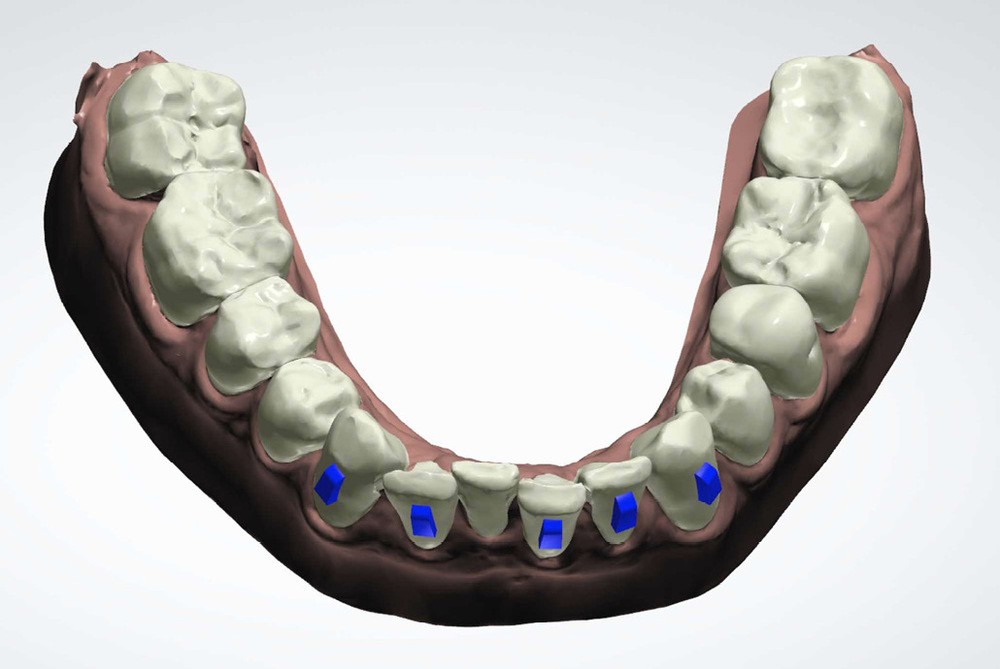

(fig. 4 à 10)

Le plan de traitement établi conjointement avec son chirurgien-dentiste traitant consiste à réaliser un alignement dentaire mandibulaire et à réaliser des extractions de 16 et 15 pour un remplacement par prothèse implanto-portée.

Le gain de place se fera par des réductions interproximales sur la zone incisivo-canine mandibulaire.

Il est décidé de ne pas redresser la 43 complètement afin de ne pas entraîner d’interférences occlusales.

Un accompagnement par des meulages occlusaux est réalisé.